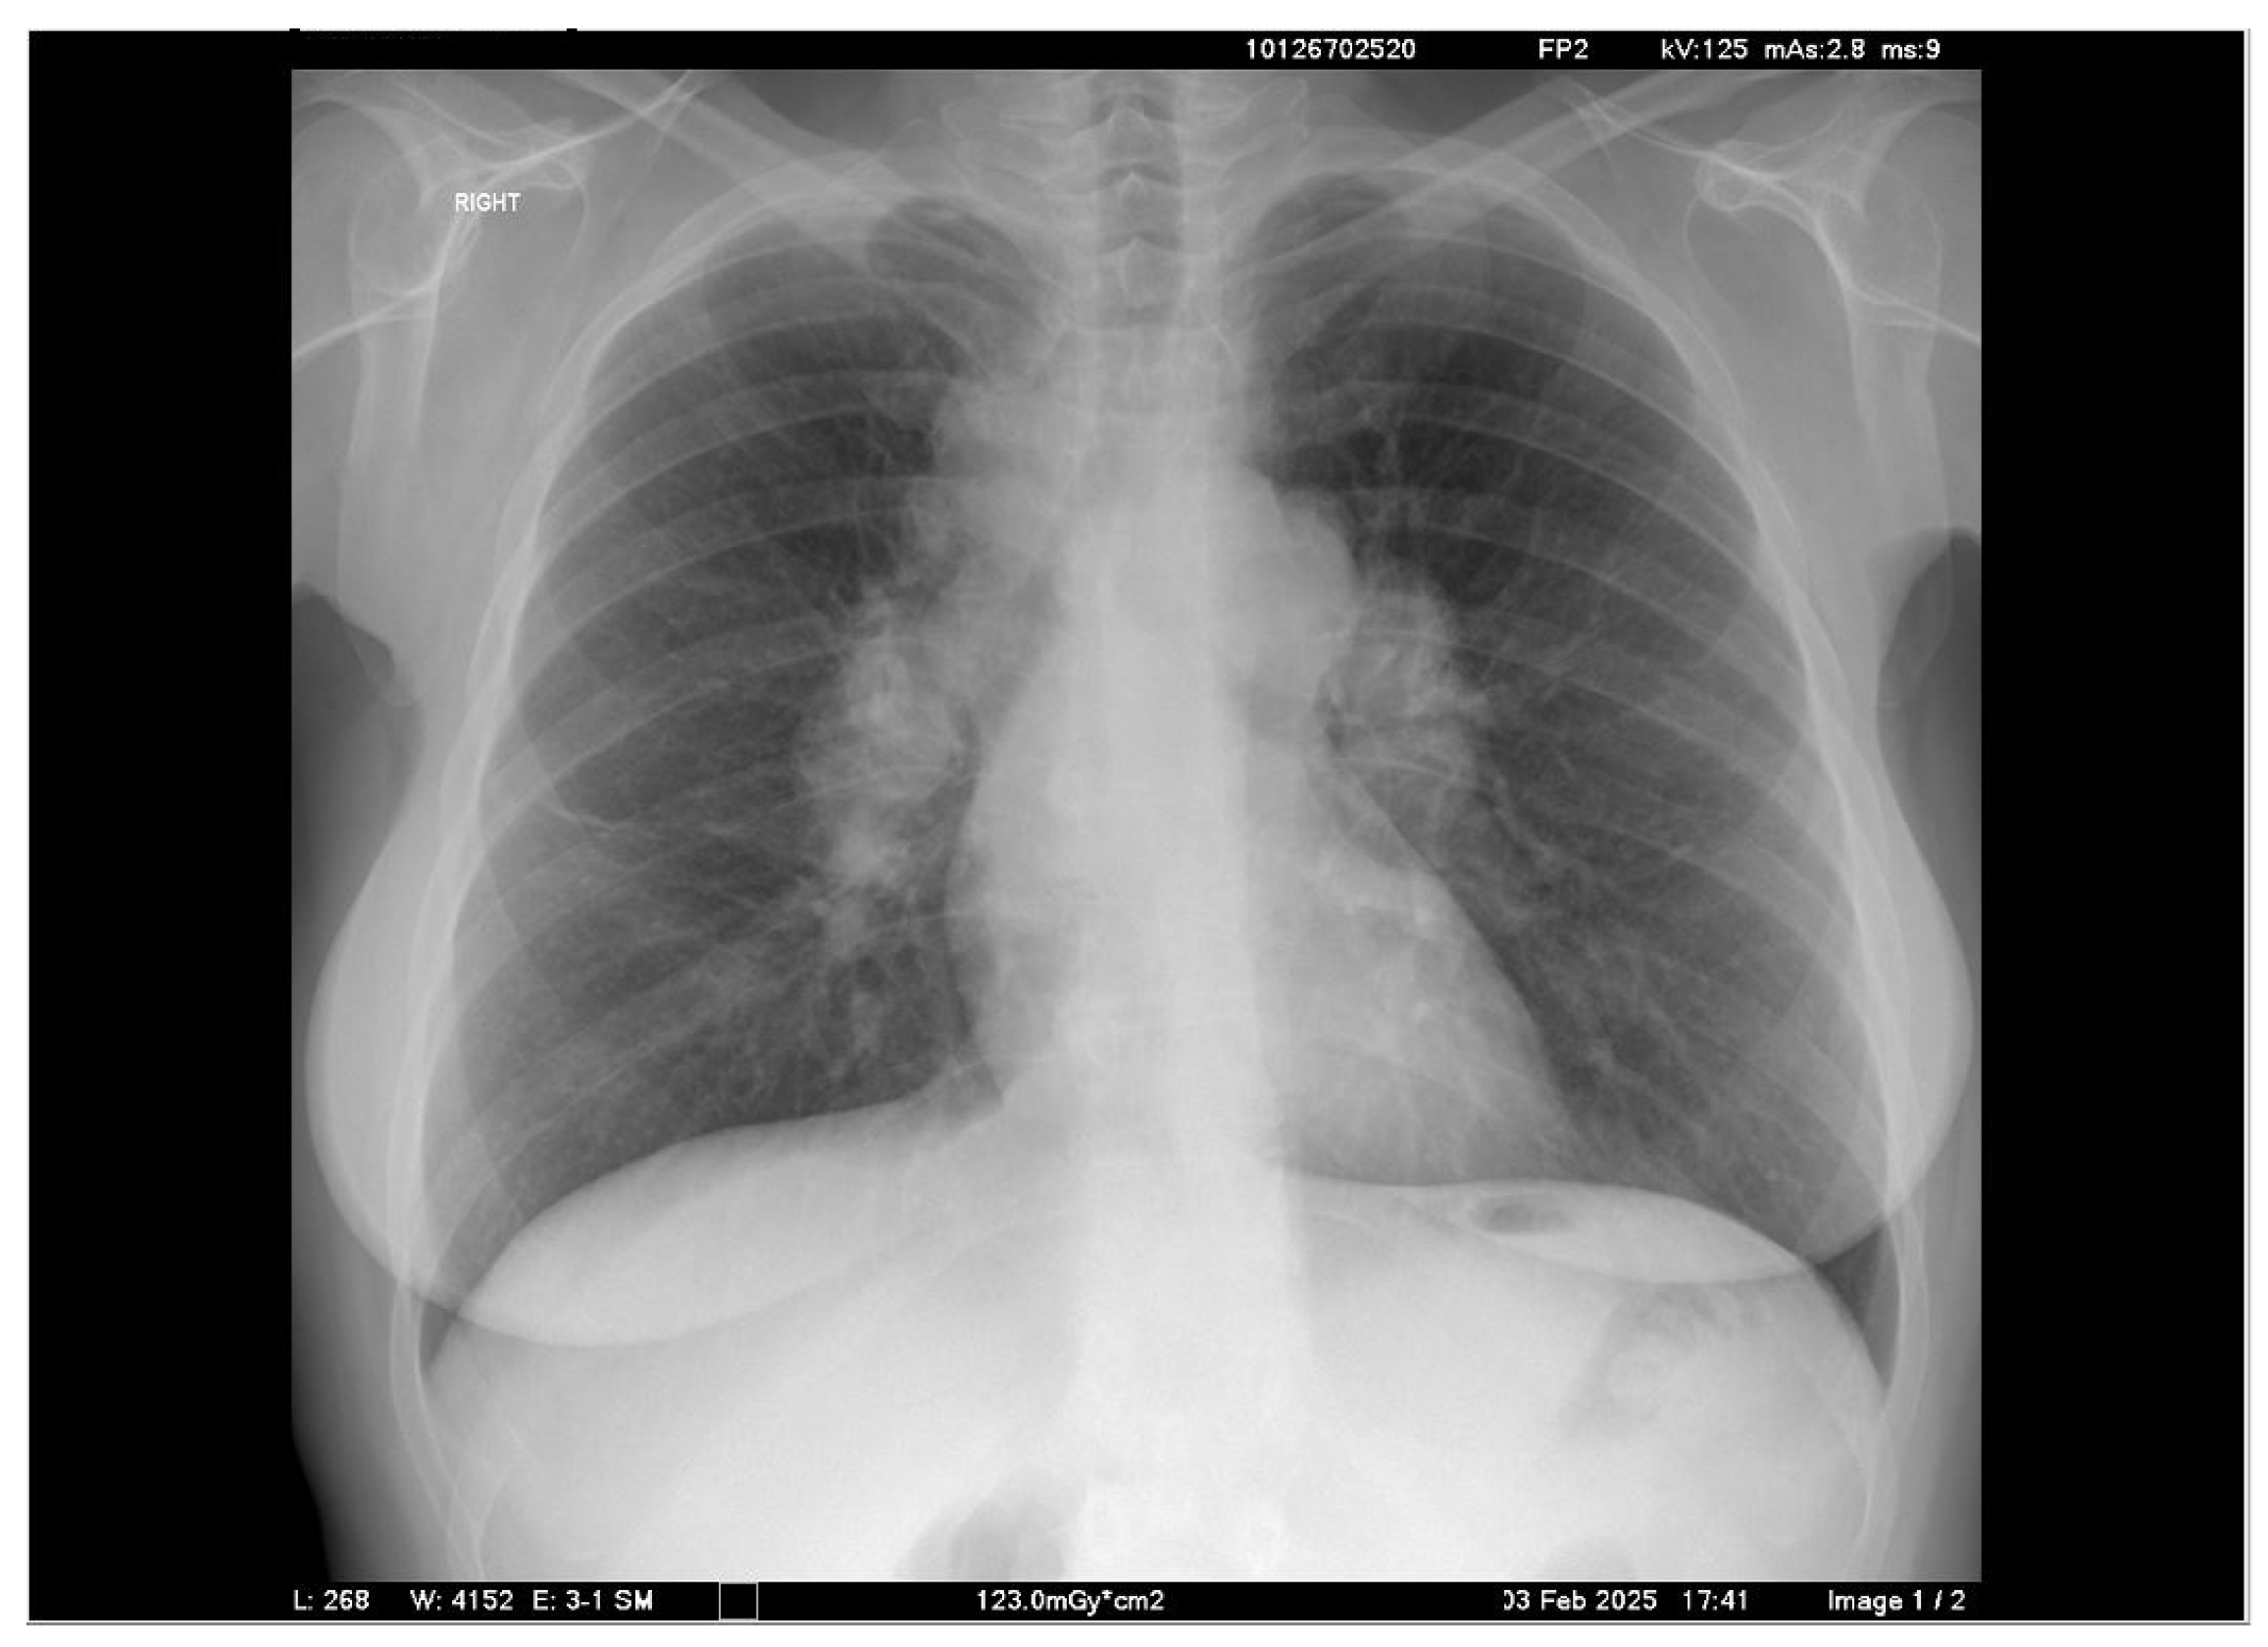

2. Case Presentation